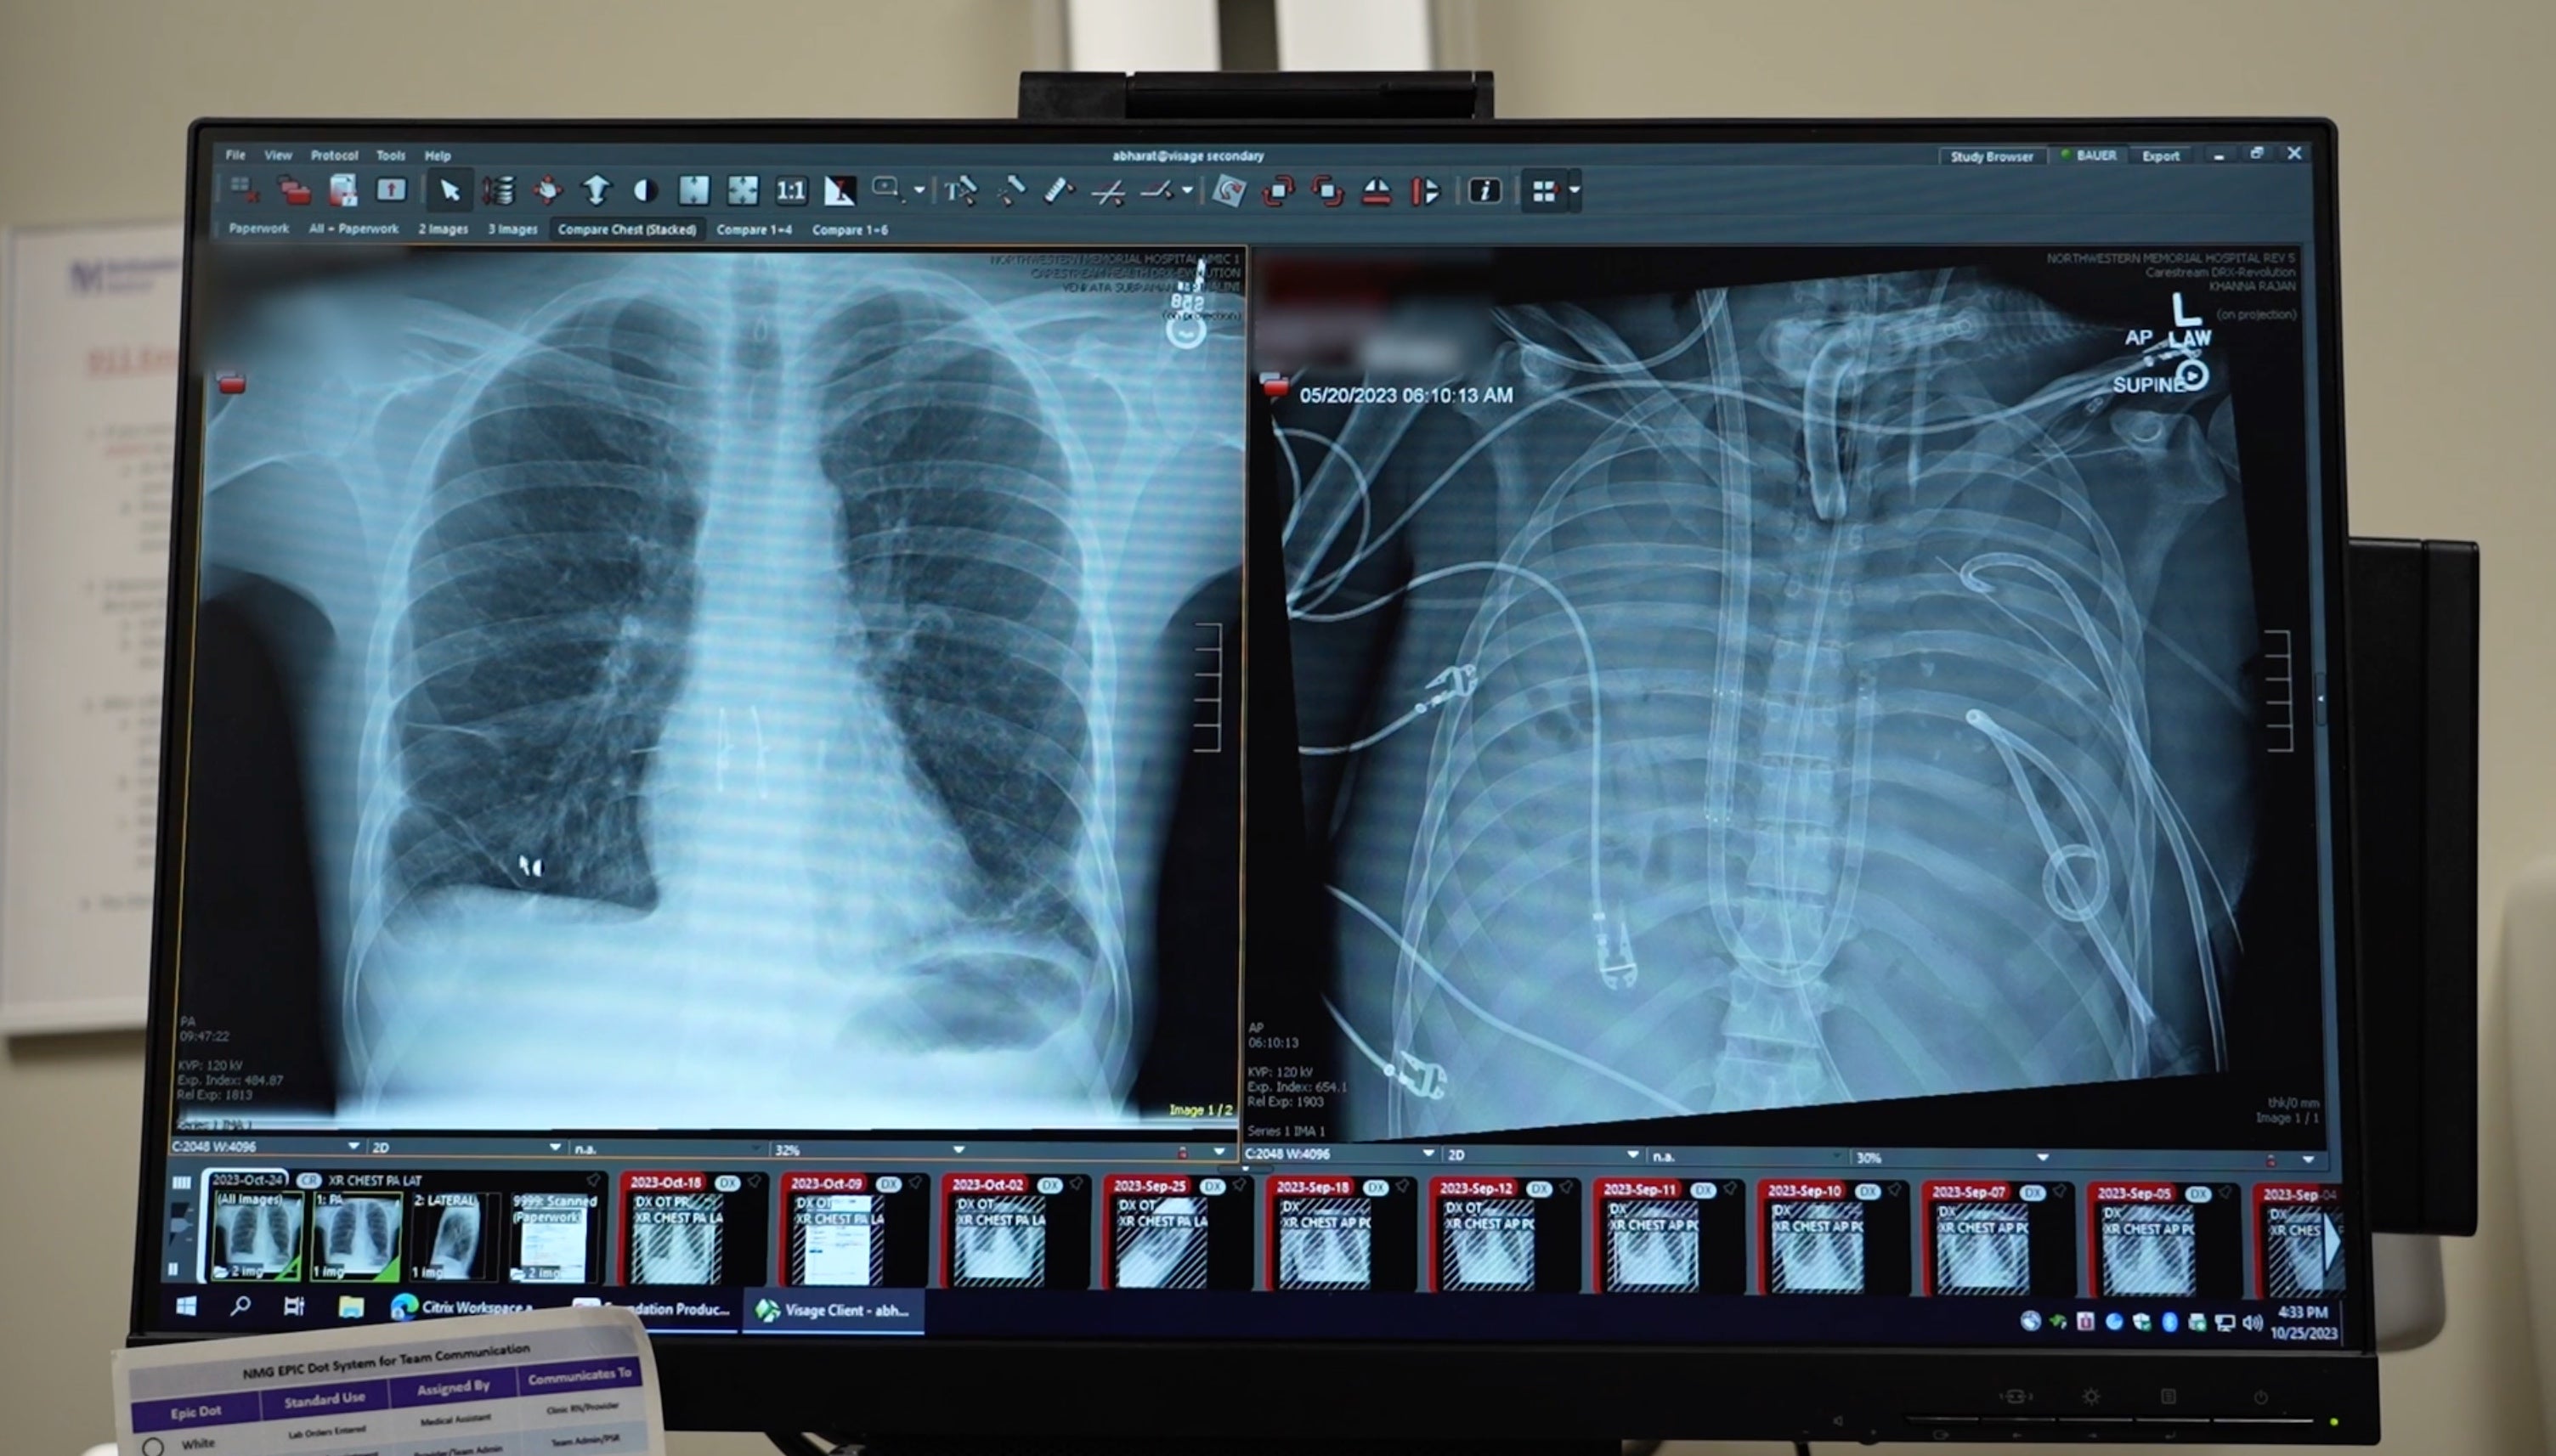

Surgeons involved in the operation, at Northwestern University in Illinois, have described how they removed the patient’s infected lungs and built an “artificial lung” to keep him alive until a double lung transplantation was available.

To save the man’s life, surgeons engineered an artificial lung system that temporarily replaced the organs’ functions. It oxygenated the blood, removed carbon dioxide, and helped maintain a stable blood flow through the heart and body.

Once surgeons removed the infected lungs, the patient’s organs and blood pressure started to recover.

After two days breathing through an artificial lung, donor lungs became available and a double lung transplant was performed.